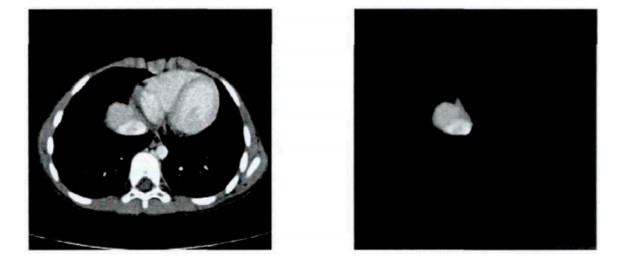

Figure 5.  Original CT image and smooth, segmented liver image

Figure 6.  Multi-threshold OTSU segmentation of the sixth layer of liver CT images